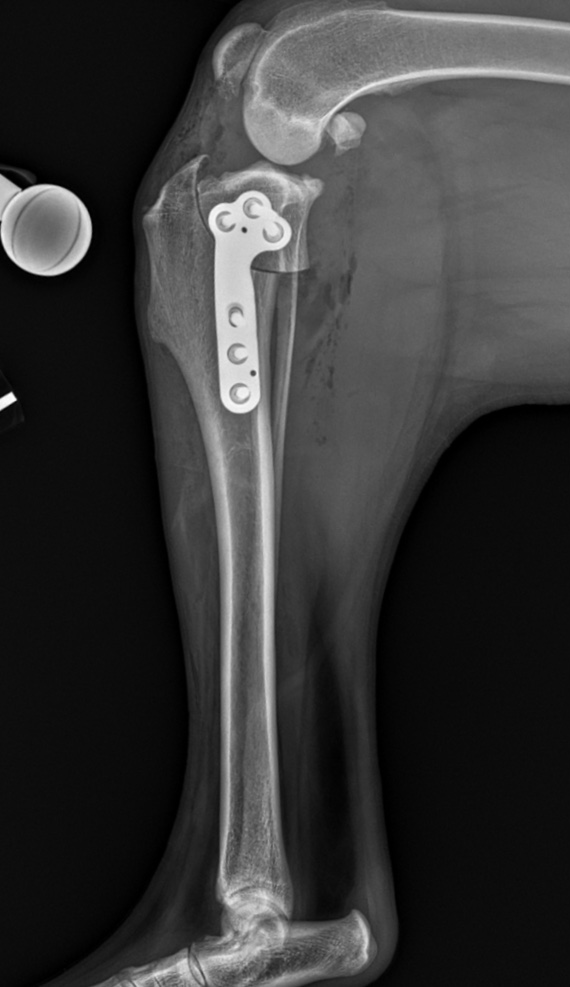

Tibial Plateau Leveling Osteotomy (TPLO)

TPLO Surgery

TPLO PostOp Xray Cary Grove Animal Hospital Cary, IL

Geometry modifying procedures are most commonly done for dogs weighing over 40 pounds who may not achieve adequate stabilization with the more basic extracapsular repair technique. The most common surgeries within this category are the Tibial Plateau Leveling Osteotomy (TPLO) and Tibial Tuberosity Advancement (TTA).  The TPLO is the gold standard as it provides the best short and long term results of all Cruciate Ligament Repair surgeries. A TPLO involves cutting the tibia to change the slope of the joint, thus changing the mechanics within the knee to provide stabilization. Bone plates are placed on the newly cut bone to secure the angles and allow the bone to heal. These bone plates are generally left in place for the life of the dog.

The TPLO surgery offers excellent long term stabilization and functionality of the repaired limb and is the gold standard procedure for most large and/or active dogs.  A drawback of the TPLO is cost, as these are more expensive than the extracapsular repair surgery.